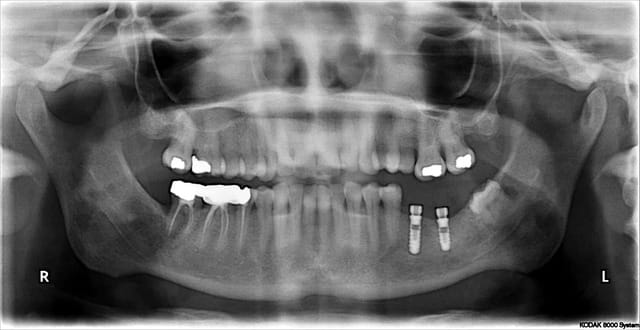

Pour vous donner du courage le cas de ce matin

Je suis très heureux de constater une telle animation sur ce sujet